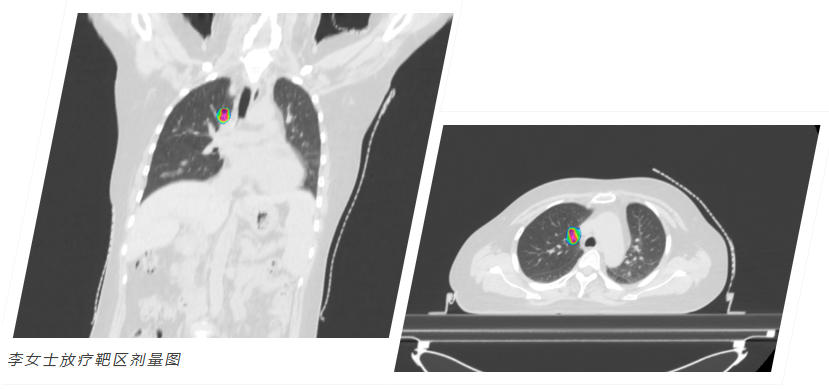

• 尖端精准诊疗

引领技术前沿

就医服务 Medical Service

选择和祐,意味着拥抱精准与前沿。我们以多学科团队(MDT)为核心,依托全球领先的质子重离子治疗系统、超弧刀等尖端设备,结合基因检测、CAR-T等先进疗法,为患者量身定制方案。在这里,科学与关怀并重,我们全程守护,为生命希望全力以赴。